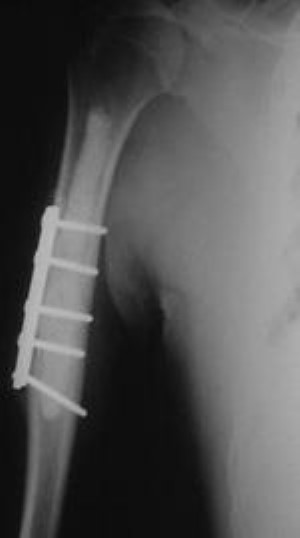

two types of hip stabilization for metastatic bone disease

A woman with advanced metastatic breast cancer to bone with pain in both her right and left hips required different types of surgery to address her problems. A special partial hip replacement was needed on the right because the hip joint was involved. On the left, a special nail was used to strengthen the femur bone below the hip.

Reproduced with permission from Weber K, Lewis V, Randall RL, Lee AK, Spingfield D: An approach to the management of the patient with metastatic bone disease, in Helfet DL, Greene WB (eds): Instructional Course Lectures, Volume 53. Rosemont, IL, American Academy of Orthopaedic Surgeons, 2004.

Lower Hip (Peritrochanteric)

Placement of a metal rod down the central canal of the femur in this location has been more successful than screw and side plate implants. Sometimes, the area is so badly destroyed that the surgeon must replace the region with a special hip replacement, especially if the metastatic bone disease is not sensitive to radiation treatment.

Below the Hip (Subtrochanteric)

The subtrochanteric area of the femur is subjected to forces four to six times a person's body weight. For this reason, pathologic fractures have difficulty healing.

• Screw and side plate constructs, along with PMMA, can be used in this area but have a relatively high failure rate and don't protect the entire bone.

• Replacements on the top of the femur bone may be necessary in extreme cases where the bone is badly destroyed.

• For lesions where a break has not yet occurred but is likely, use of a metallic nail is the ideal option.